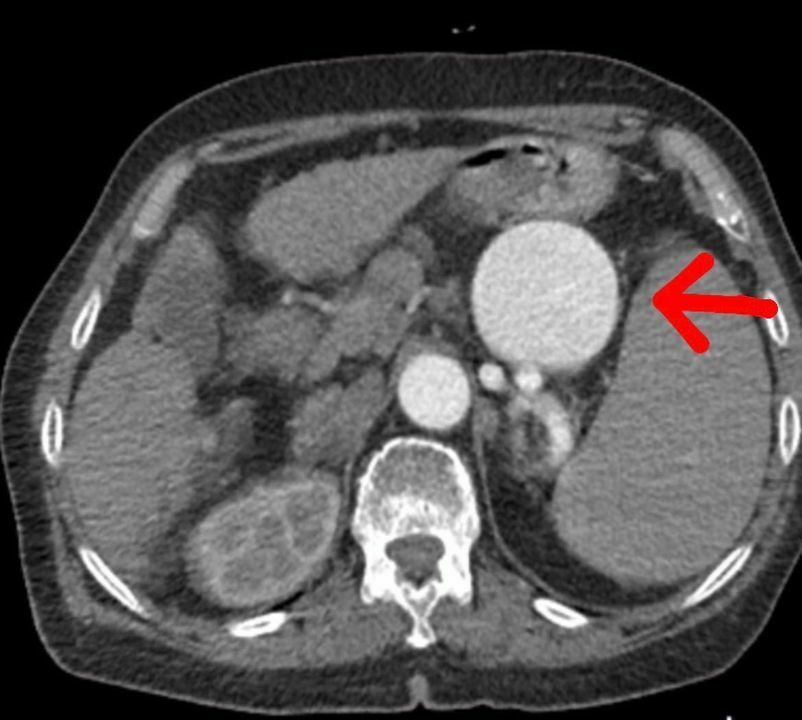

Op. Dr. Volkan Burak Taban, hastanın gastroenteroloji kliniğinden kendilerine geldiğini belirterek, 'Yapılan tomografide dalak arterinde oldukça geniş, dev diyebileceğimiz bir anerizma olduğunu gördük. Bu durum, hastanın hayatını tehdit ediyordu. Multidisipliner bir değerlendirme yaparak, hastayı açık cerrahi ile tedavi etmeye karar verdik' dedi.

Hastanın Şırnak'ta ameliyat edilmesinin riskli olduğunu belirten Dr. Taban, 'Öncelikle anjiyo yoluyla dalak anerizmasını kapatmayı denedik. Ancak başarısız olunca açık cerrahiye geçtik. Açık cerrahi operasyonu ile dalak arterindeki baloncuk başarıyla onarıldı' şeklinde konuştu.